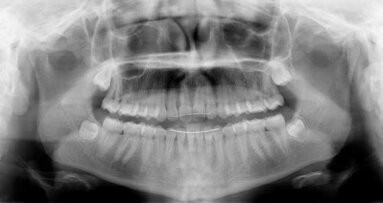

And these days that covers a lot of territory: hardening of the arteries, heart disease, diabetes, liver cancer, blood cancer, kidney cancer, pancreatic cancer, Alzheimer’s, preterm babies, poor digestion, poor wound healing, obesity, poor sleep quality and, perhaps most critical of all, inflammation with no anatomical borders — all have scientific evidence connecting them to oral health.

There are always new procedures, new instruments and new techniques to try. And our patients demand us to be on the leading edge of what’s out there in the media. Patients are online Googling “mouth and body health” before their appointments. They’re researching antibiotics and wisdom teeth, and they have access to much of the same information that we do. Patients want to know about the oral systemic link, and we need to be prepared for that.